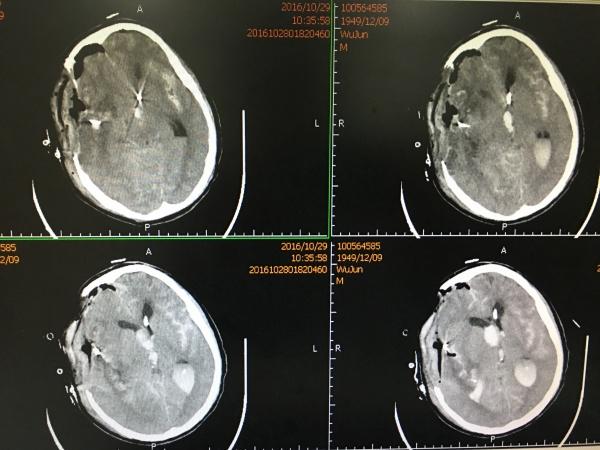

我们急诊在全麻下行开颅血肿清除+动脉瘤夹闭+颅内压监护探头植入术,术后复查头颅CT如下:

手术顺利,效果满意,术后第4天再次复查头颅CT:

见MCA供血区大面积梗塞,查凝血无明显异常,予以改善微循环、扩容等对症治疗,1周后再次复查CT: